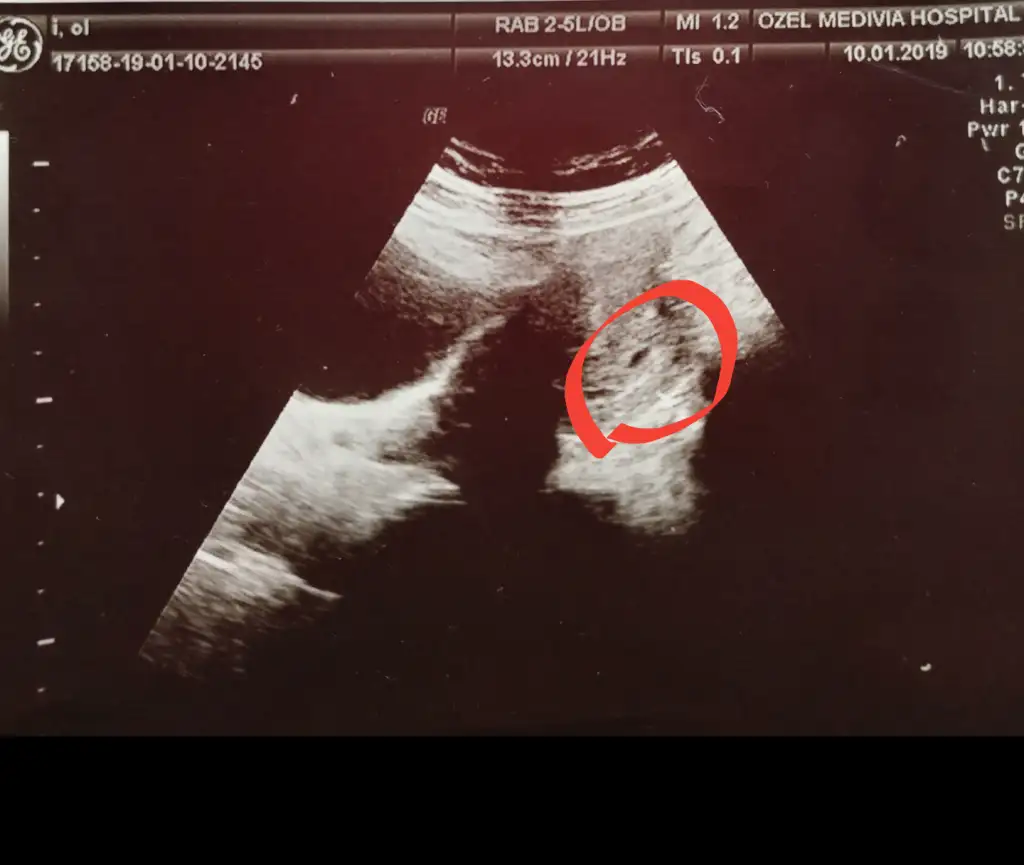

Hayirli olsun canim bende haftaya gtcem insallah gorurumBen de geçtiğimiz cuma 5.haftamı doldurdum. İlk muayenemdi ve çok heyecanlıydım. Keseyi zar zor gördük ve sanki 4.5 haftalık gibi dedi doktor. O yüzden gelecek cuma bir daha gel 6.haftanı da doldurmuş olacaksın dedi. Ultrason fotoğrafı da aşağıdaki gibi hiç keseye de benzemiyor benceEki Görüntüle 2544868

Karından ultrasonla baktı. İnşAllah cuma günü kesem normal büyüklüğünde görünür. Kalp atışını da duyarsam benden mutlusu yok.